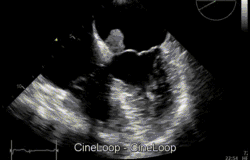

Bardzo często śluzak serca wykrywany jest po zatorowym udarze mózgu, lub po zatorze obwodowym. W diagnostyce bardzo ważna jest echokardiografia uzupełniana badaniami tomografią komputerową lub rezonansem magnetycznym[2].

Śluzak serca – najczęstszy łagodny nowotwór serca, występujący trzykrotnie częściej u kobiet, rozwijający się z wsierdzia ściennego[2]. Pojawia się niemal wyłącznie w przedsionkach, najczęściej w lewym – w 86%[3], może pojawić się w każdym wieku, ale szczyt występuje między czterdziestym, a pięćdziesiątym rokiem życia[2]. Jest rozrostem polipowym. W typowej postaci ma on kształt kulistego, miękkiego zgrubienia na cienkiej nóżce (szypule), zawierającej wiązkę naczyń odżywiających, która umożliwia przemieszczanie się guza. Przemieszczanie się śluzaka przez zastawkę mitralną, lub trójdzielną może powodować ich dysfunkcję z objawami niedomykalności zastawki mitralnej, lub niedomykalność zastawki trójdzielnej i/lub zwężenia (stenozy)[2]. Cały nowotwór jest pokryty śródbłonkiem. W około 10% przypadków śluzak serca występuje rodzinnie jako składowa zespołu Carneya. U pacjentów często obserwuje się tzw. Triadę objawów: